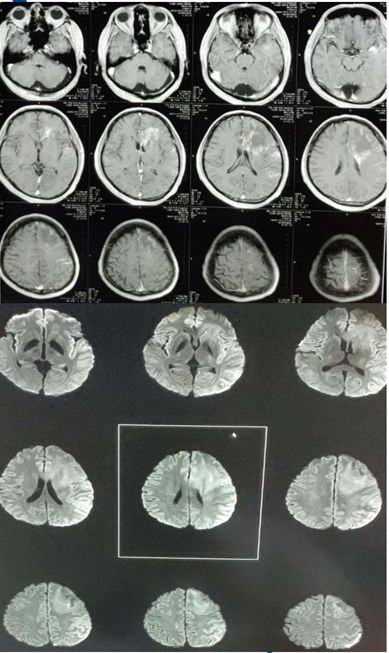

女患,15岁,主因双眼上翻,下颌阵挛2天来诊,伴发热,体温38-39度,发作性左侧上下肢、左侧口角强直-阵挛。入院查体:记忆力较前明显下降, 左侧肢体轻偏瘫(左上肢4+,左下肢5-)。

答案:Rasmussen脑炎

诊断依据:①右侧半球;多灶性,轻偏瘫,认知下降;②视频脑电图(VEEG):EPC,PET:右侧半球代谢减低;抗癫痫药物疗效差;③术后病理:脑组织小胶质细胞和T细胞浸润。

Rasmussen脑炎:为单侧性大脑半球受累为主的进展性疾病,常规抗癫痫药物治疗无效,局灶性发作为其主要特点,部分性癫痫持续状态(EPC)为其发作的主要表现形式,多伴有受累侧半球相关的运动和认知功能减退。RE主要的病理特点:局限于受累大脑半球的炎性疾病,以T细胞浸润、小胶质细胞增生、小胶质结节形成,以及随后出现的神经元脱失、星形细胞增生等为主要表现形式。MRI特点岛叶及岛叶周围出现轻度局灶性大脑皮质萎缩;同侧脑室扩大;大脑皮质和(或)皮层下T2和FLAIR像的高信号;尾状核头部信号增高或萎缩。在上述改变未发生之前可先出现一过性大脑皮质局部肿胀。